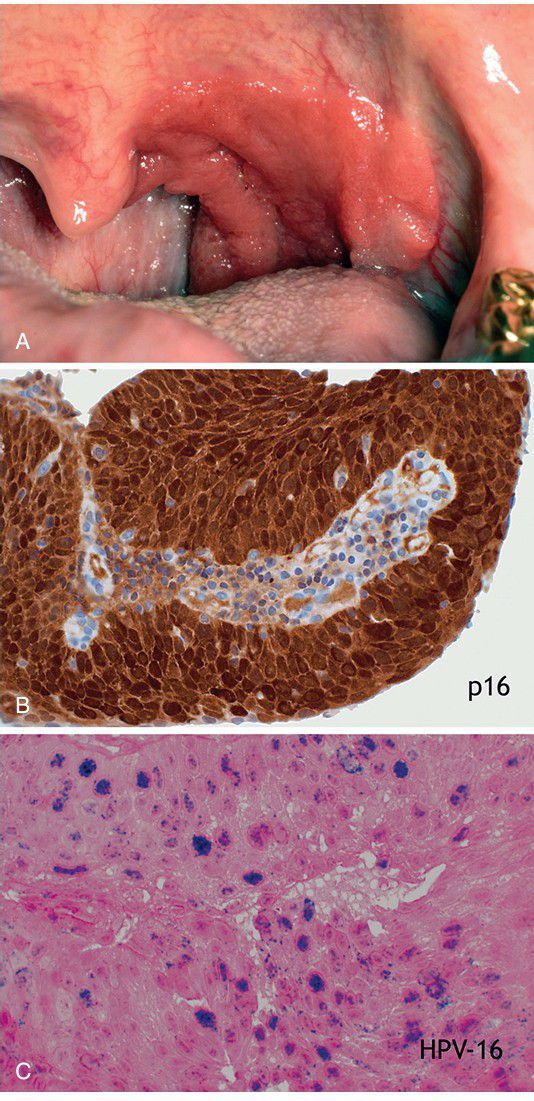

. A, Large, erythroplakic lesion involving the left soft palate and tonsillar region. B, Immunohistochemical staining showed the tumor to be positive for p16, which is a surrogate marker for transcriptionally active, high-risk human papilloma virus (HPV) infection among oropharyngeal squamous cell carcinomas. C, In situ hybridization (ISH) demonstrated the presence of intranuclear HPV 16 DNA.